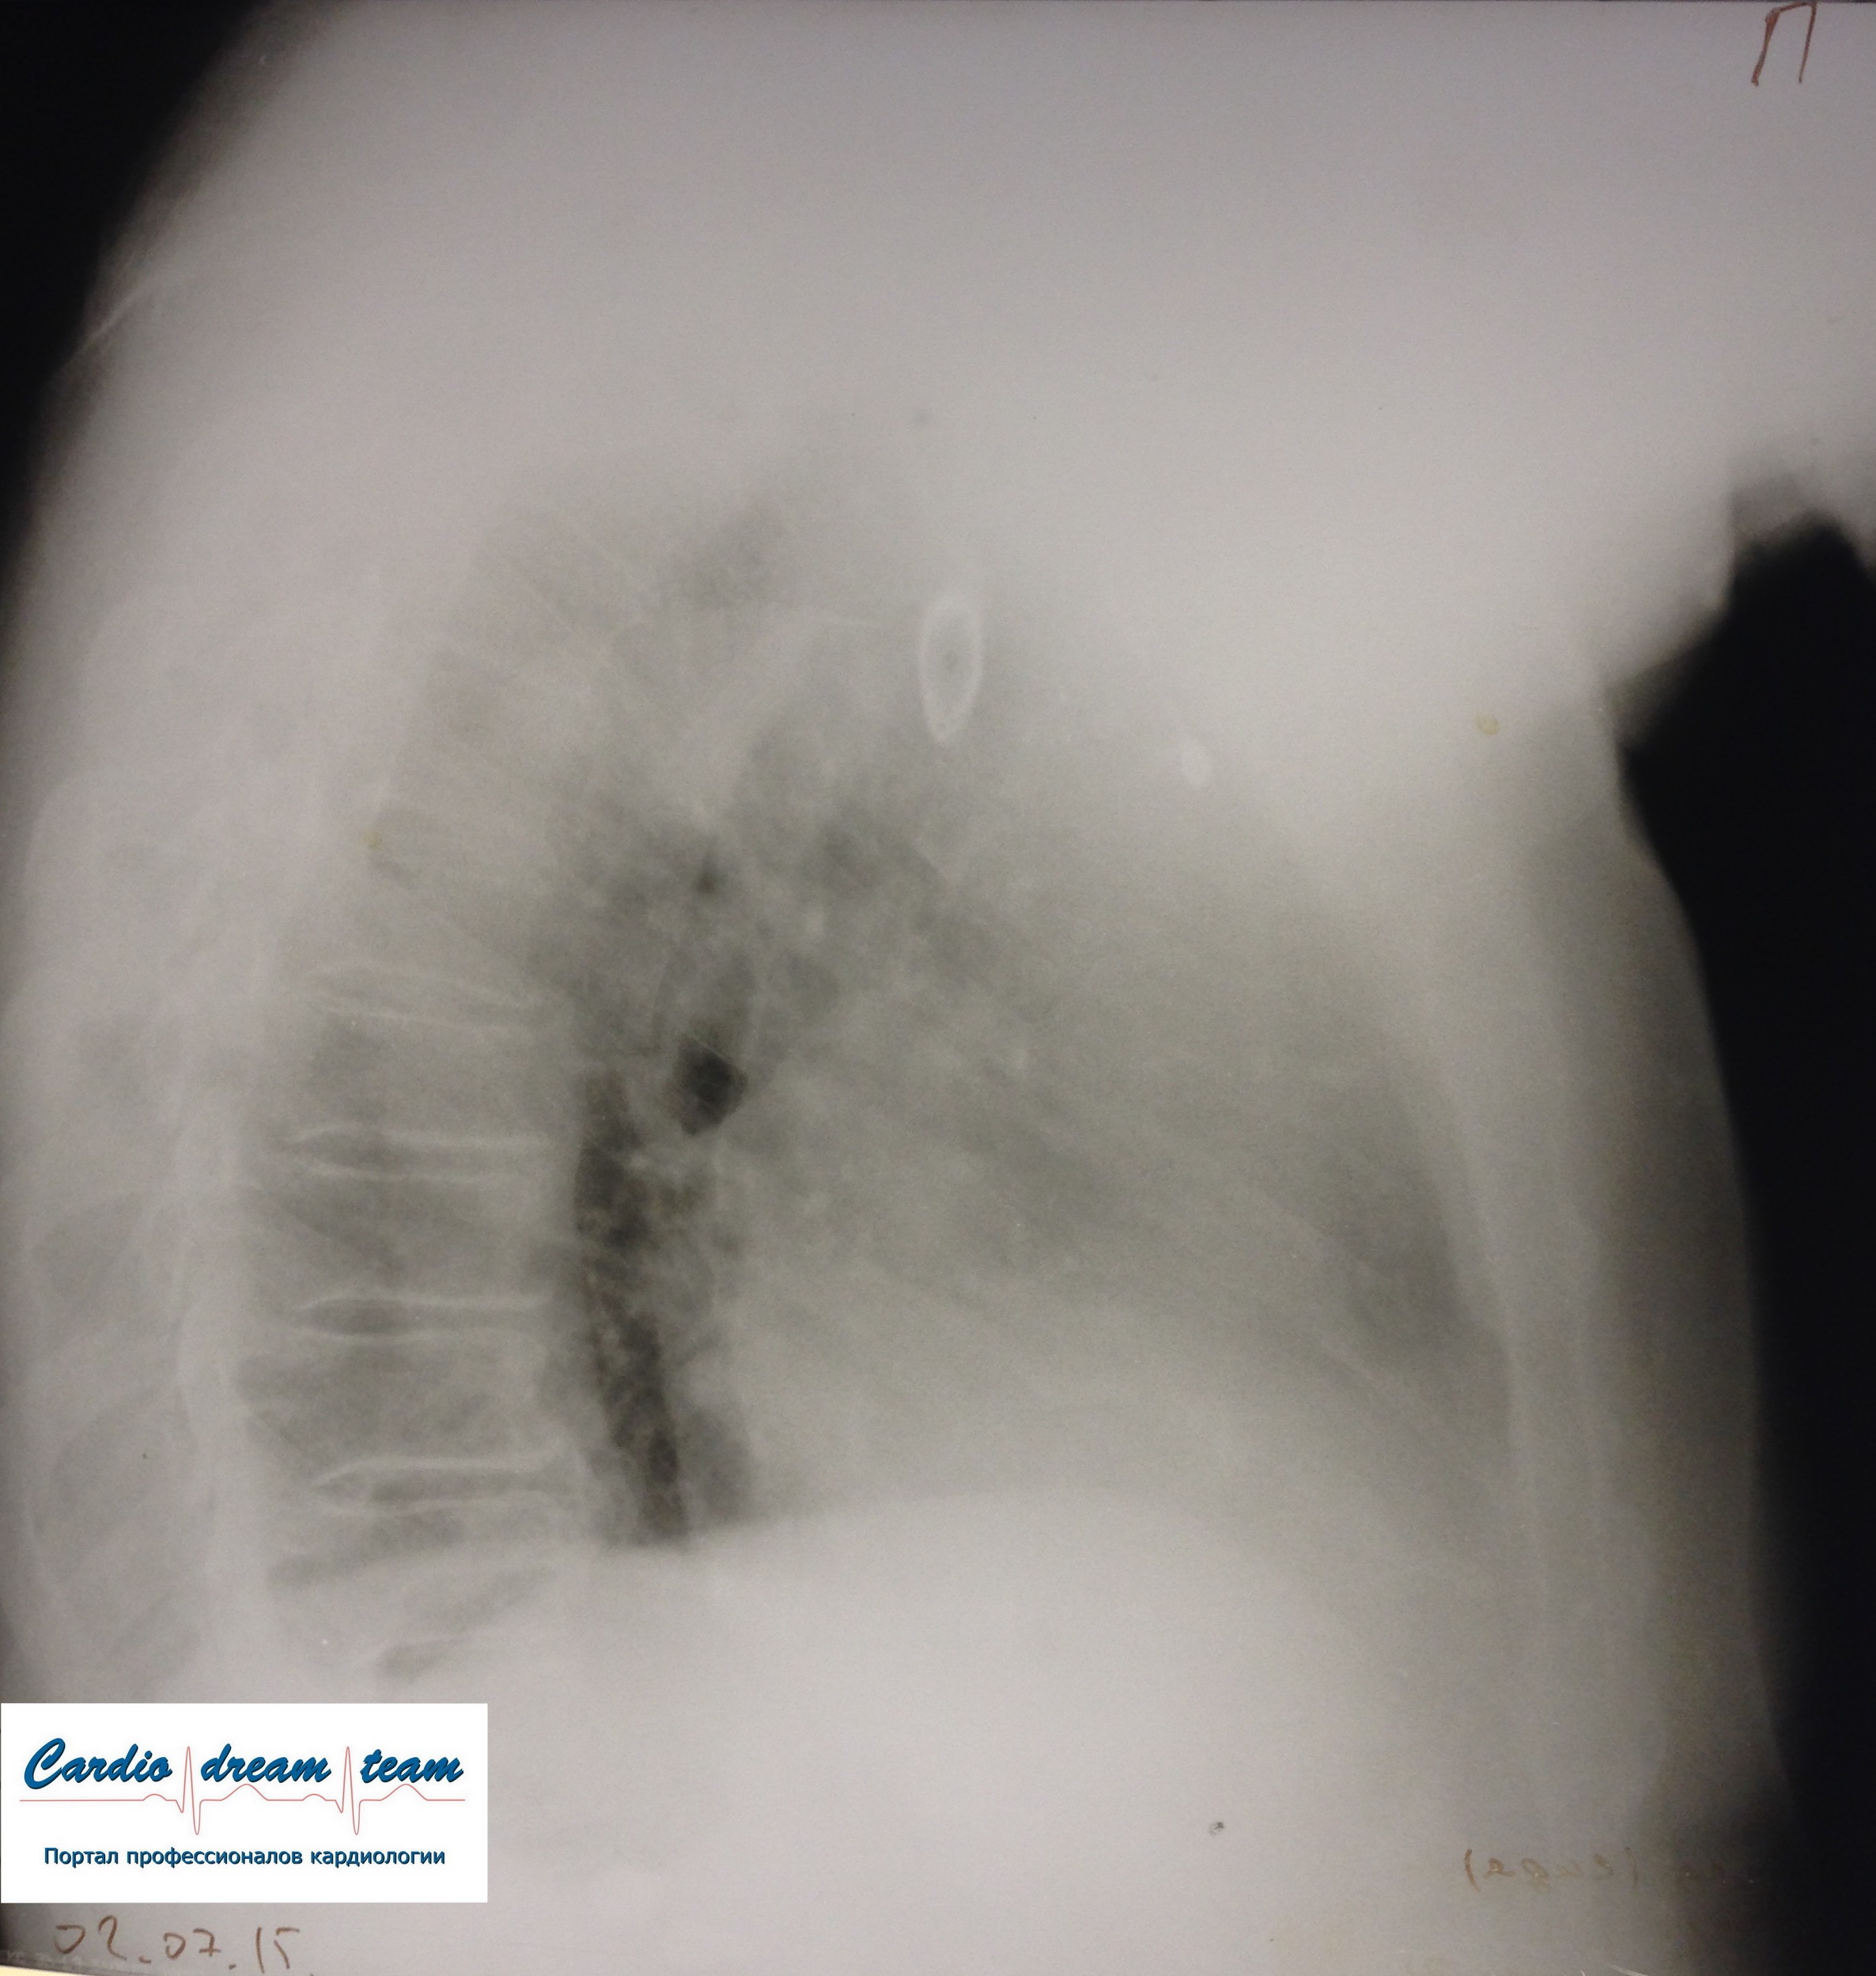

M, 71.

ТЭЛА. Есть увеличение правых отделов сердца. Давность около недели поэтому уже инфаркт пневмония слева с экссудативным плевритом, который виден очень хорошо.